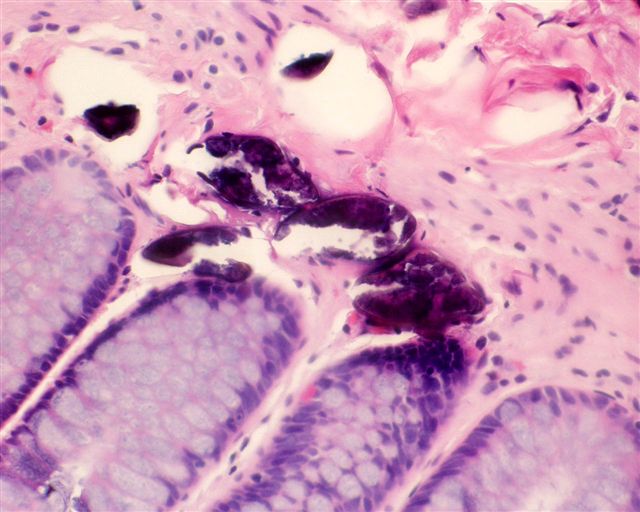

Microscopic (histologic) description

- Ova are mainly seen in the loose submucosa of large intestine, usually with formation of granulomas and infiltration by eosinophils and inflammatory cells

- Later the muscularis mucosa becomes involved and the overlying mucosa shows small superficial ulcers

- Fibrosis develops in chronic stage, when only calcified eggs are seen

Microscopic (histologic) images

Contributed by Nalini Bansal Gupta, M.D., Lisa Cerilli, M.D. and @zaalruwai83 on Twitter